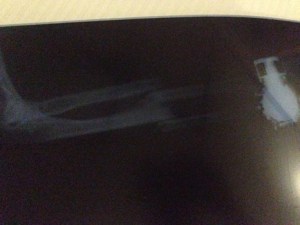

A few hours later, the orthopaedic surgeon came to see my arm. I had severely dislocated both the Ulna and Radial bone in my arm and urgently required surgery. He tried to convince me to have an operation in Zanzibar but Dr Metha’s advice was ringing in my ears: no way was I getting an operation here. I was wheeled into the emergency room where he gave me a backslab cast. With no painkillers, he twisted and prodded my arm back into some sort of alignment. This was one of the most painful experiences in my life (the most painful experience was when I decided to get a tongue ring). Juan experienced a similar story and got a cast on his ankle. I later learnt that it’s normal to get morphine in developed countries.

We checked ourselves into the emergency room at the Sandton Mediclinic (Private hospital). I was asked to take xrays again (post backslab) and wait for further treatment. This is a great hospital, run with efficiency and very comfortable even if they kept asking for medical insurance and payment information. The emergency doctor Dr Mwunze was amazing and was keen to help. She called the orthopaedic surgeon on call who quoted at least R100,000 (USD 10k) to insert metal plates into my arm. They needed at least R50k deposit to secure the operation.